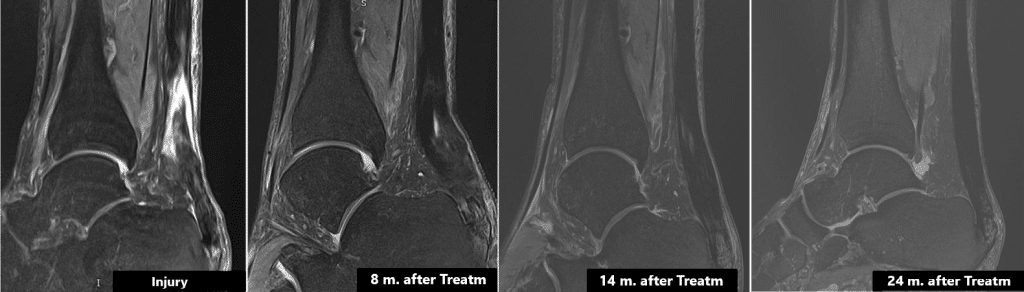

We have clinical experience with virtually every tendon in the human body, namely the patellar tendon, the Achilles tendon and the Harmstring, to mention just a few. MRI from a 86 years-old patient is included below. He presented a frayed Achilles tendon, with a 3 cms break. The evolution of the injury after treatment him with cultured stem cells can be observed. 8 months later, the injury was virtually healed and 24 months later, the tendon was brand new and completely unlike the previously frayed tendon.

Manuel Monzó, 74-years-old patient, had been suffering pain for 10 years, because of a rupture on the Achilles tendon.

For the first time in history, 20 million cultured stem cells were implanted in the Achilles tendon. After 8 months his injury had almost disappeared and a year later he had a brand new tendon.